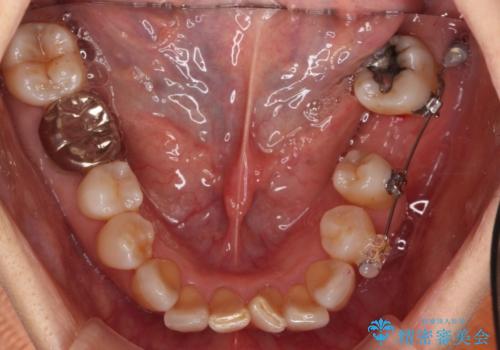

抜歯後に部分的にワイヤー矯正を半年ほど行ってから、ブリッジを入れる治療を行いました。

奥歯の部分矯正を行うことで、歯の傾きが良くなり、結果神経を取らずにブリッジを入れていくことができました。

通常矯正治療後は歯並びが戻らないように保定が必要ですが、ブリッジを入れているので歯並びは戻らないため保定が不要です。

部分矯正と補綴の相性は良いといえます。